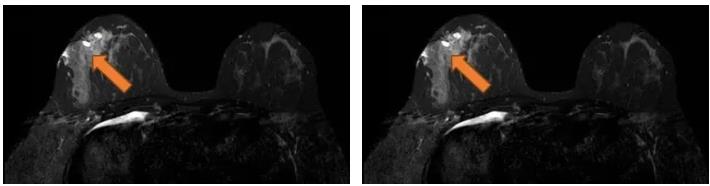

2021.7.7乳腺MRI:右乳外上象限肿物(BI-RADS-6)3.1cm×1.9cm×3.0cm,右腋窝见肿大淋巴结,M灶可能。

右乳外上象限见不规则肿块,呈长/稍长T2、等T1信号,DWI呈高信号,ADC图信号减低,ADC值约0.863,增强扫描明显强化,TIC呈Ⅲ型,大小约3.1×1.9×3.0cm,邻近皮肤增厚,皮下脂肪层模糊,另肿块外侧旁见小肿块影,增强明显强化,与外上象限肿块相连。右侧腋窝见肿大淋巴结。

图3. 乳腺MRI

(3 cycle 后)2021.9.22 复查乳腺MRI示:右乳肿块较前减小14mm×9mm×18mm。

图7. 乳腺MRI